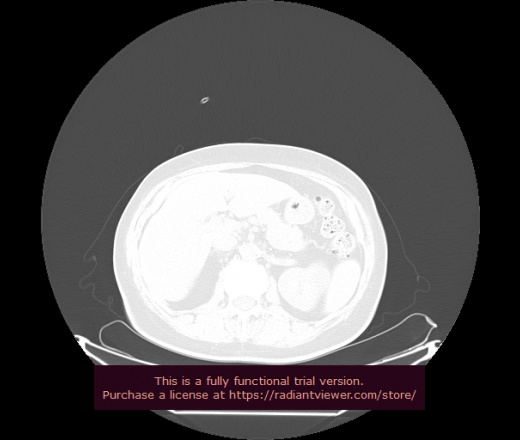

Уважаемые коллеги, если имеется интерес, сможете ли Вы спрогнозировать дальнейшее +-одинаковое течение процесса у 4 данных разных пациентов? Зацепиться где-то можно очень просто, где-то нельзя.